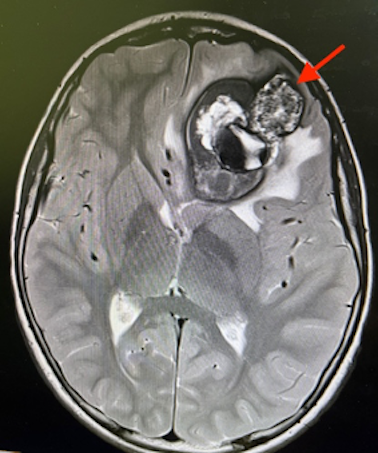

Gli esami ematici risultano nella norma, ma gli esami di imaging neuroradiologico (RM encefalo e angioRM) rivelano la presenza di cavernomi cerebrali multipli, uno più voluminoso in sede frontale sinistro con recente sanguinamento, associato a edema e discreto effetto massa (Figura 1 e 2)). Necessario quindi trasferimento in Neurochirurgia per intervento e in programma consulenza genetica.